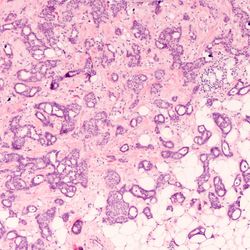

Leveraging Next-Gen IHC Tools to Advance Precision Oncology Research

Harnessing the power of multiplexing and RNA–protein studies could help design targeted cancer treatments

A “Whole Person” Approach to Histology

Pathologist and assistant professor Rebecca Waters, DO, on finding “zebras” and her osteopathic medicine background

The Role of Cytology in the Fight Against Disease

How cytologists continue to meet the ever-increasing need for diagnostic screening